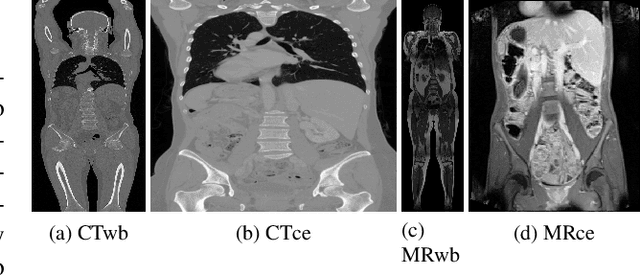

Abstract:Despite the recent successes of deep learning, such models are still far from some human abilities like learning from few examples, reasoning and explaining decisions. In this paper, we focus on organ annotation in medical images and we introduce a reasoning framework that is based on learning fuzzy relations on a small dataset for generating explanations. Given a catalogue of relations, it efficiently induces the most relevant relations and combines them for building constraints in order to both solve the organ annotation task and generate explanations. We test our approach on a publicly available dataset of medical images where several organs are already segmented. A demonstration of our model is proposed with an example of explained annotations. It was trained on a small training set containing as few as a couple of examples.